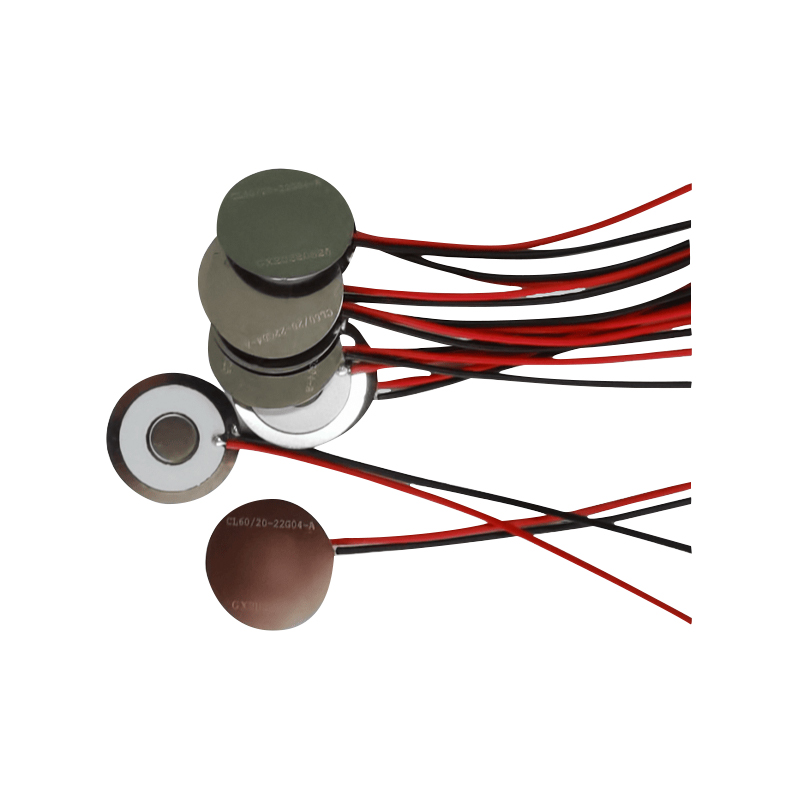

মেডিক্যাল মেশ নেবুলাইজার ট্যাবলেটগুলি হল শ্বাস-প্রশ্বাসের মাধ্যমে বিভিন্ন শ্বাসযন্ত্রের ব্যাধি যেমন হাঁপানি, এবং দীর্ঘস্থায়ী অবস্ট্রাকটিভ পালমোনারি ডিজিজ (সিওপিডি) ইত্যাদির চিকিৎসার জন্য ওষুধ বা দ্রবণকে ক্ষুদ্র অ্যারোসল কণাতে রূপান্তর করতে মেডিকেল ডিভাইসে ব্যবহৃত নির্ভুল উপাদান। নেবুলাইজার শীটের নকশা এবং উপাদান নির্বাচন কার্যকর ওষুধ সরবরাহ এবং রোগীর আরাম নিশ্চিত করার জন্য গুরুত্বপূর্ণ। স্টেইনলেস ডায়াফ্রাম শীটটি একটি নির্ভুল লেজার প্রক্রিয়ায় লেজার ড্রিলিং প্রযুক্তির মাধ্যমে ইস্পাত শীটে হাজার হাজার ক্ষুদ্র 2-3μm জালের ছিদ্র দিয়ে পাঞ্চ করা হয় এবং তারপরে এটি পিজোইলেকট্রিক সিরামিক রাউন্ড শীটের সাথে শক্তভাবে বন্ধন করা হয়, যা পাইজোইলেকট্রিক শীটের রেজোন্যান্ট ফ্রিকোয়েন্সিকে পিসি-ইলেকট্রিক শীট-এর মাধ্যমে উচ্চ শক্তির শক্তিতে রূপান্তরিত করে। বোর্ড, এবং দ্রুত ভেঙ্গে যায় তরল ওষুধ সূক্ষ্ম অ্যারোসল কণাতে। এই ফোঁটাগুলিকে মাঝারি কণার আকারও বলা হয়, যখন মাঝারি কণার আকার D50 শতাংশ> 60% বা তার বেশি পৌঁছায়, তখন কণাগুলি ফুসফুসের গভীরে অ্যালভিওলির পৃষ্ঠে শ্বাস-প্রশ্বাসের সাথে পৌঁছানোর জন্য যথেষ্ট ছোট হবে, এইভাবে ওষুধের শোষণের দক্ষতা এবং থেরাপিউটিক প্রভাবকে উন্নত করবে। মেডিকেল মেশ মাইক্রো মেশ নেবুলাইজার শীটে প্রধানত বিভিন্ন ফর্ম বিদ্যমান, স্টেইনলেস স্টীল মাইক্রো জাল নেবুলাইজার শীট, নিকেল প্যালাডিয়াম মেডিকেল নেবুলাইজার শীট, পিআই পলিমার মেডিকেল নেবুলাইজার শীট এবং আরও অনেক কিছু। উপরের সবগুলোই পাইজোইলেকট্রিক সিরামিক কম্পন শক্তি রূপান্তরের মাধ্যমে পরমাণুকরণ প্রভাব অর্জন করে।